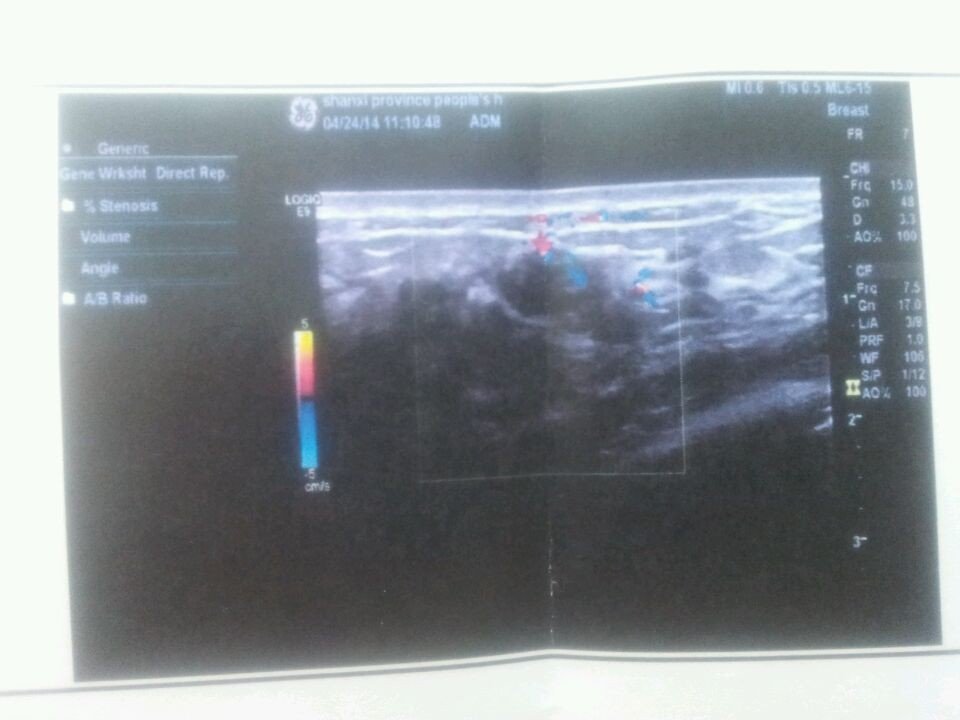

怀孕一个月,左乳房一周前有轻微疼痛,现痛感消失,超声诊断报告单显示如下: 乳腺:左右侧腺体厚度分 别为1.7cm,1.6cm, 左乳2点距乳头约2.2cm腺体内可见低回声结节,大小约1.2cm X0.5cm, 边界清,内可见血流信号,余腺体结构正常,分布均匀,血流分布正常.请问什么意思?有事吗?需怎么治疗? 孩子能不能要? 点击展开 匿名用户 2014-04-24 13:34 为您推荐: 其他回答 应该是乳腺纤维瘤,良性的,不影响要孩子的。 匿名用户 2014-04-24 14:15 相关问题 患者曾因乳腺癌切除一侧乳房,胸部疼痛并连续低烧突然转高烧怎么回事? 关于乳房疾病我今年40岁,乳房无硬块,有乳腺增生,最近有一侧有个地方疼痛,碰到就痛,您能告诉我这是怎 怀孕34周,乳房针扎一样的痛,怎么缓解疼痛?

别为1.7cm,1.6cm, 左乳2点距乳头约2.2cm腺体内可见低回声结节,大小约1.2cm X0.5cm, 边界清,内可见血流信号,余腺体结构正常,分布均匀,血流分布正常.请问什么意思?有事吗?需怎么治疗? 孩子能不能要?